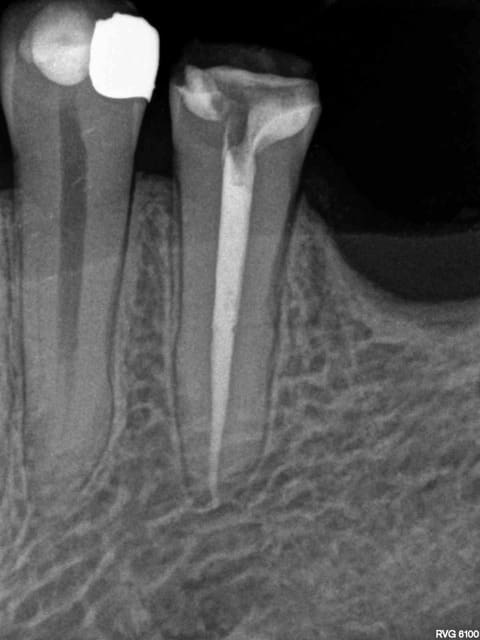

> ton obturation en mésial ne va pas à l'apex!

A l'apex radiologique c'est sur. Compter 0,5 à 1 mm en moins pour l'apex physiologique.

> > ton obturation en mésial ne va pas à l'apex!

> A l'apex radiologique c'est sur. Compter 0,5 à 1 mm en moins pour l'apex

> physiologique.

Ah d'accord donc tu as un dépassement sur la racine distale?

On n'a pas parlé de la distale mais c'est vrai que pour moi c'est nettement plus chiant à reprendre que la mésiale. Pour enlever toute cette substance radioopaque il faut beaucoup aléser, et il en restera toujours.

Oui -)))) postes un peu des radios de tes endos micro métrées pour voir.

La radio cone en place était un peu plus sexy. Mais ca ce sont les aléas du système B. Pour 80 boules je ne me fais pas chier à tout reprendre. ( canaux mésiaux en y tu noteras)